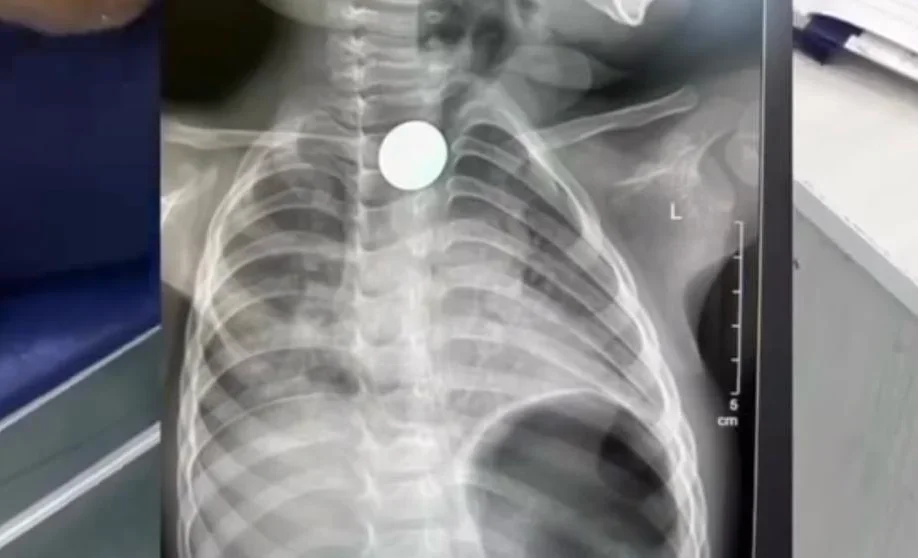

По данным медиков, маленького пациента направили в Бишкек из Нарына. Монета застряла во втором физиологическом сужении пищевода. Из-за сложности расположения предмета врачи в трех предыдущих больницах, куда обращались родители, не смогли его извлечь.

Специалисты столичной детской больницы применили малоинвазивный метод с использованием катетера Фолея, что позволило достать монету без разрезов и операции.